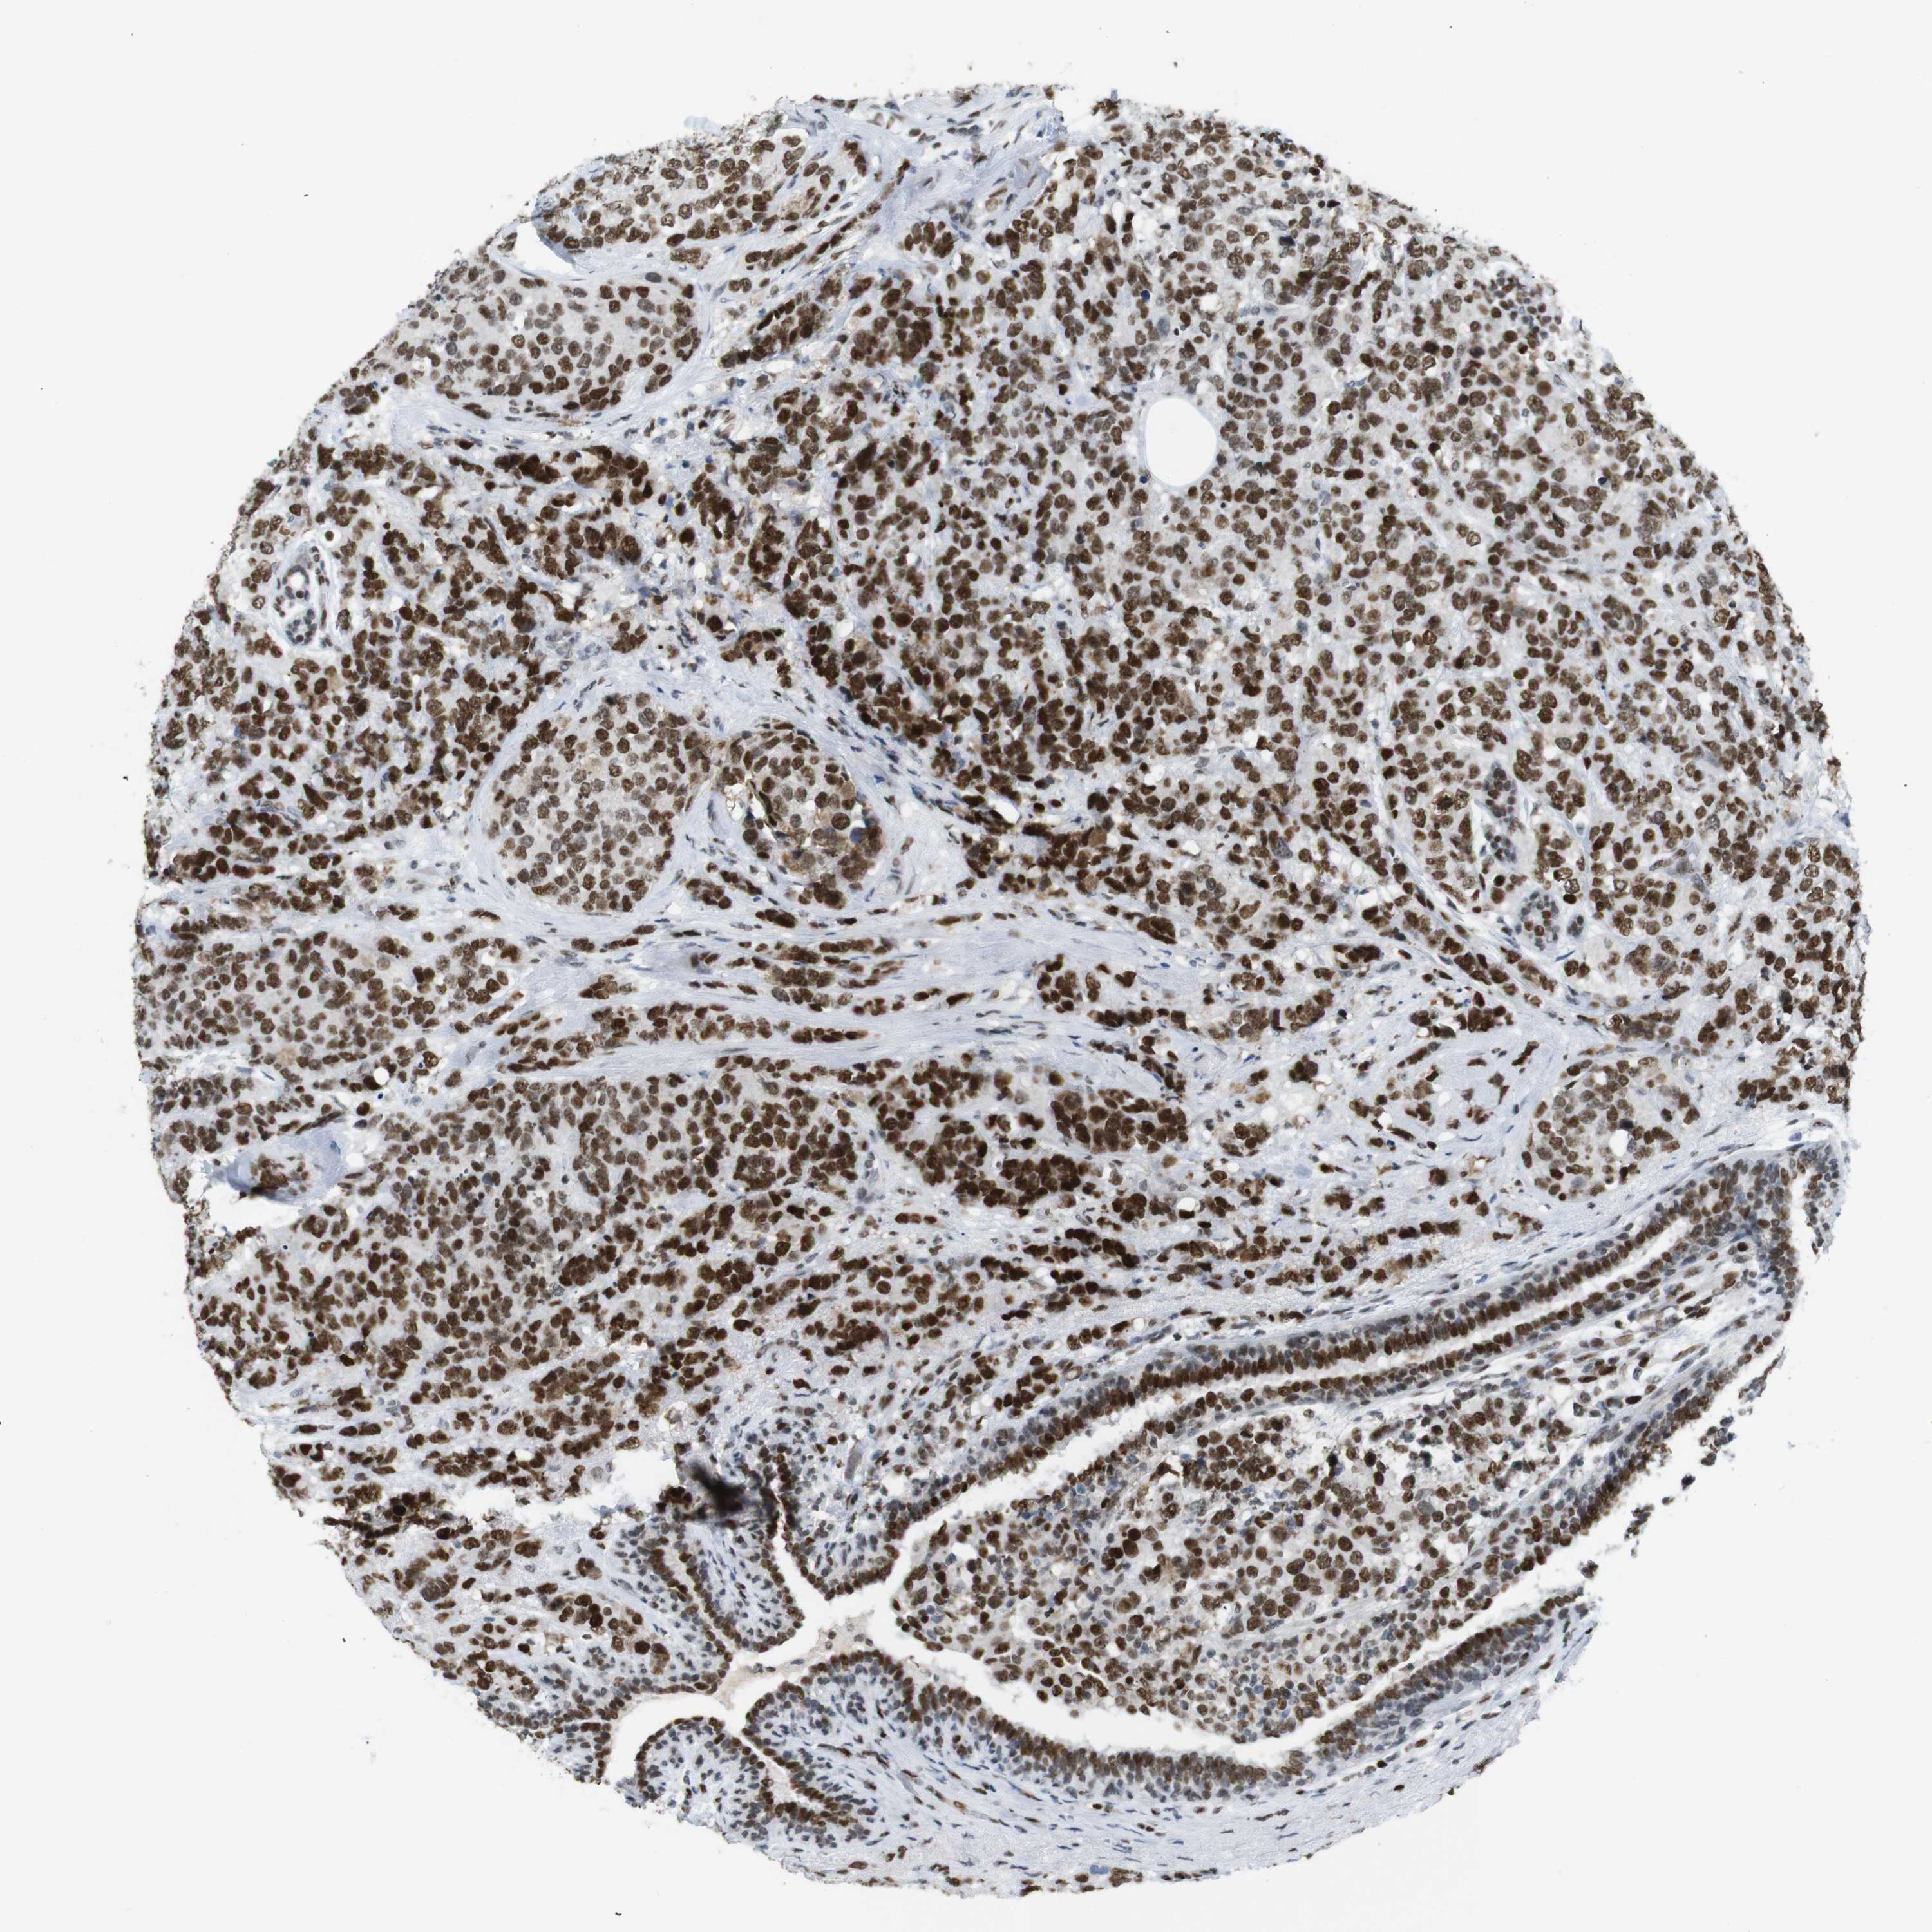

CANCER BREAST CANCER Show tissue menu

BRCA TCGA BRCA VALIDATION PROTEIN EXPRESSION

RIOX2 is potential prognostic, high expression is unfavorable in Breast Invasive Carcinoma (TCGA)